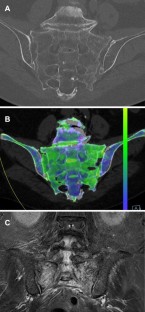

As the average age of society increases, so does the number of cases of fragility fractures of the pelvis (FFP). Magnetic resonance imaging (MRI) can visualise associated oedema and is thus the gold standard for diagnosing such fractures. MRI, however, is costly, not always available, and involves certain exclusion criteria. Dual-energy computed tomography (DECT) appears to be a promising alternative. It is unclear, however, whether it could be used for diagnosing FFP with similar sensitivity/specificity. The aim of our study was thus to compare conventional CT and DECT with MRI in cases of suspected FFP.

With 100% sensitivity and specificity, DECT is on par with MRI when it comes to diagnosing fragility fractures of the pelvis and is superior to conventional CT (90.3% sensitivity, 100% specificity). In terms of classification as well, there were no differences between DECT and MRI. On conventional CT, on the other hand, 16 patients were classified differently than they were on MRI.

Our study shows DECT to be reliable and superior to conventional CT in terms of oedema detection and specific fracture classification in FFP. DECT thus combines the advantages of conventional CT (good visualisation of bone matter) and MRI (medullary cavity and visualisation of occult fractures).